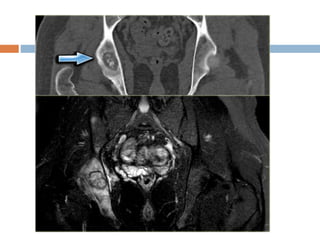

Xray

 Well defined radiolucent cyst

 Trabeculated and eccentrically placed

 In growing tubular bone, vertebrae and flat

bones

 In adult may confuse with GCT

 Marked ballooning of bone end